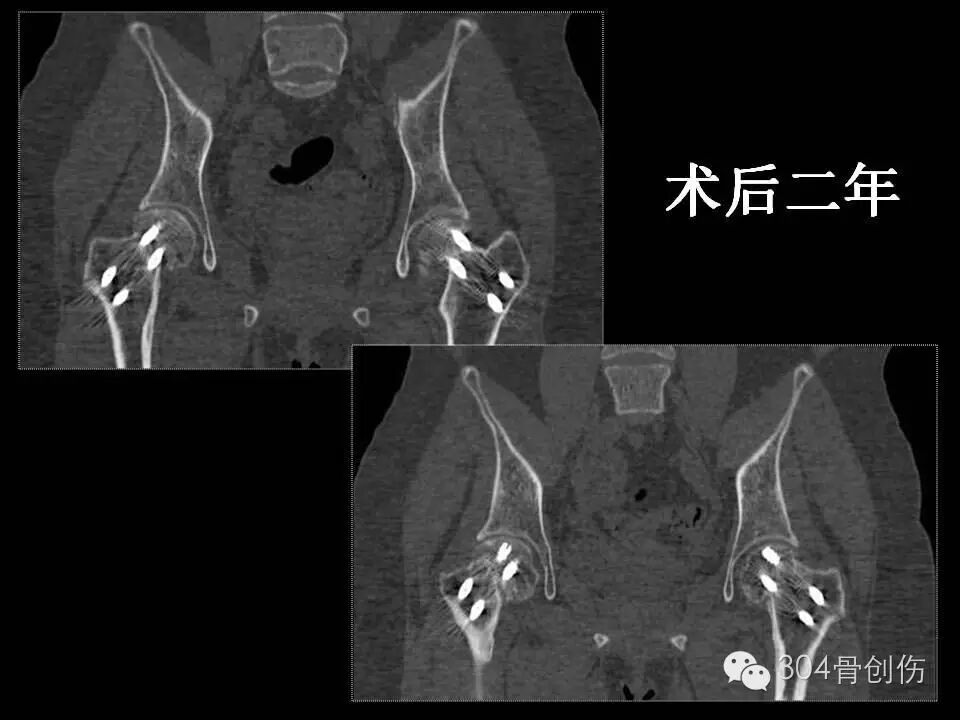

术后6个月患髋部X线显示,股骨颈有短缩,螺钉少许退钉,骨折基本愈合,骨折愈合左侧优于右侧。术后1年,股骨颈未继续缩短,左侧股骨颈完全愈合,右侧股骨颈略差,行走时右髋偶感不适。术后2年随访时(图),双侧股骨颈骨折愈合,患者步态正常(图)。

怀孕期间会骨折吗?-怀孕期

图-术后X线片

图-术后两年X线片